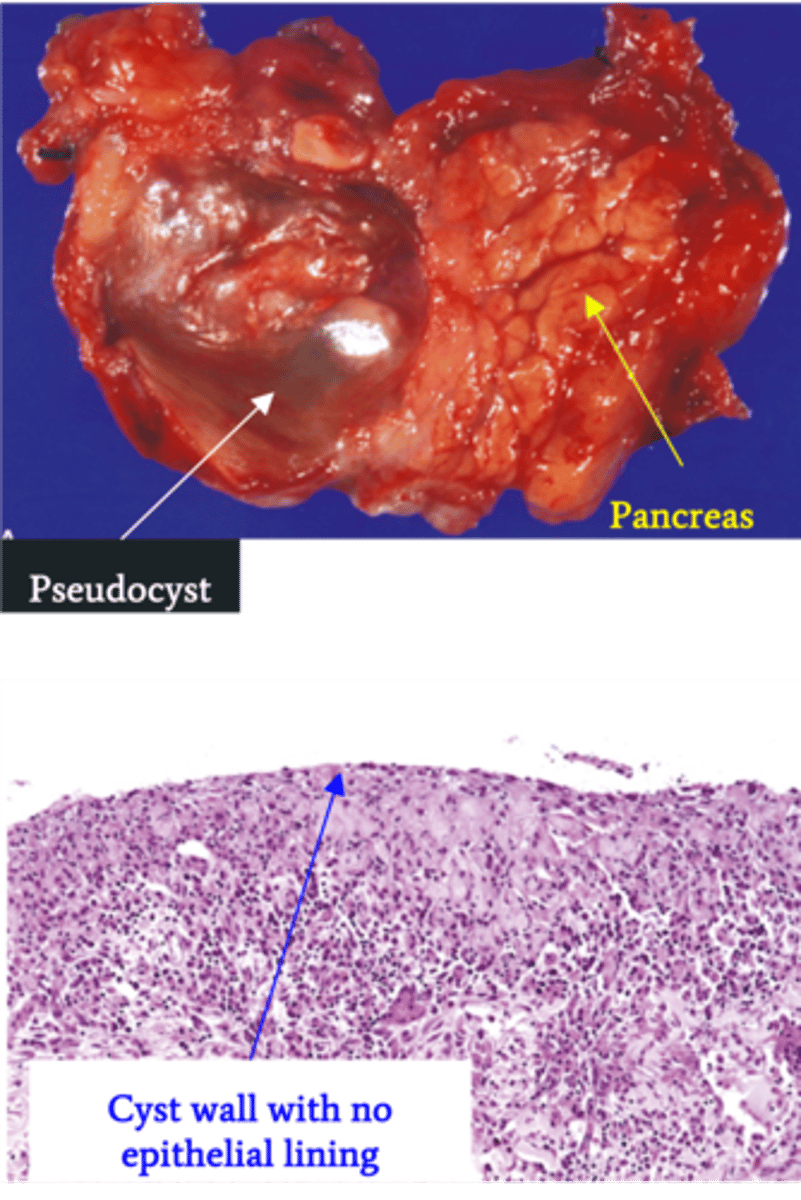

Pancreatic Pseudocyst

Define Condition:

Encapsulated collection of fluid formed by fibrous/granulation tissue surrounding liquefactive necrosis and pancreatic enzymes (no epithelial lining of cyst)

-Hx: Weeks after episode of Acute Pancreatitis

-Prog: Usually resolves spontaneously but may be infected & ruptured --> release of enzymes into abdominal cavity